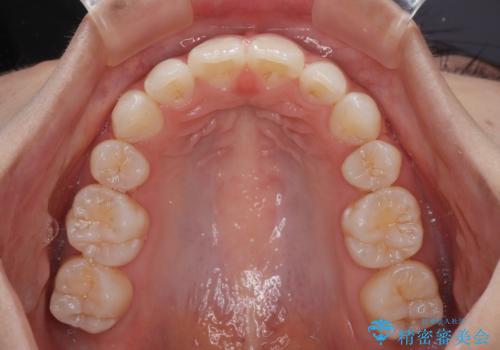

下唇に前歯が当たって跡が残ってしまう状態でしたが、スッキリとした口元に仕上げることができました。

- 口を閉じたときに飛び出してしまう上顎前歯を気にして来院された患者様です。

下顎はデコボコが気になっていたため、上下左右第一小臼歯4本を抜去して、ワイヤー装置にて口元の突出感を改善するよう矯正治療を行うこととしました。